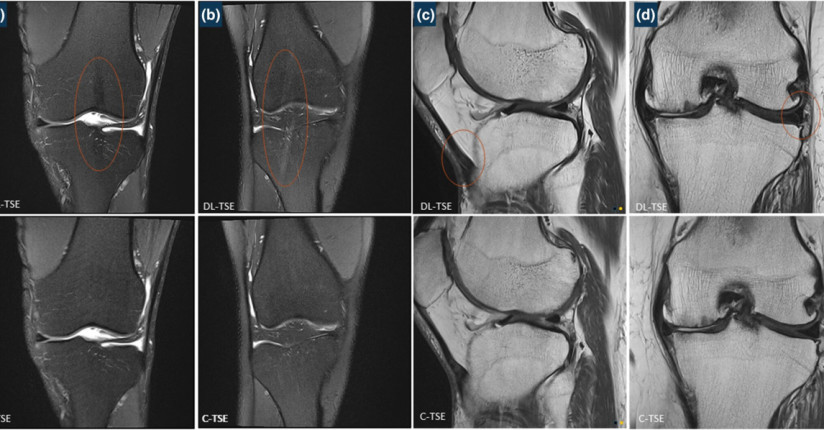

Deep-Learning TSE imaging can provide enhanced knee images

Pacific Radiology doctors and clinical staff recently contributed to a published study on conventional vs deep learning MRI.